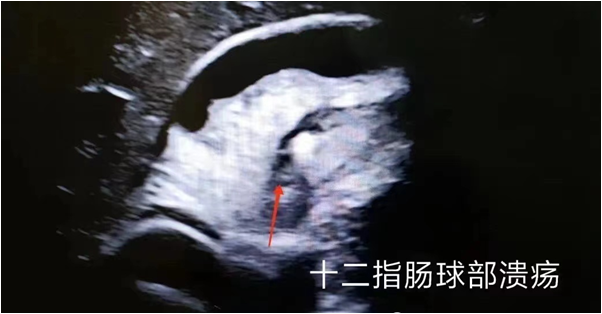

1、胃器质性病变:胃炎、胃溃疡、胃癌、胃间质瘤、胃壁异位胰腺、胃底静脉曲张、食管裂孔疝、贲门失弛缓症、十二指肠憩室等。